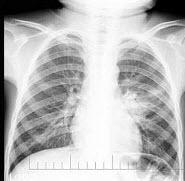

251、单项选择题

男,9岁,常年咳嗽,无其他自觉症状,X线检查如图,最可能的诊断是

A.结核瘤

B.原发性肺癌

C.炎性假瘤

D.纵隔肿瘤

E.韦格肉芽肿